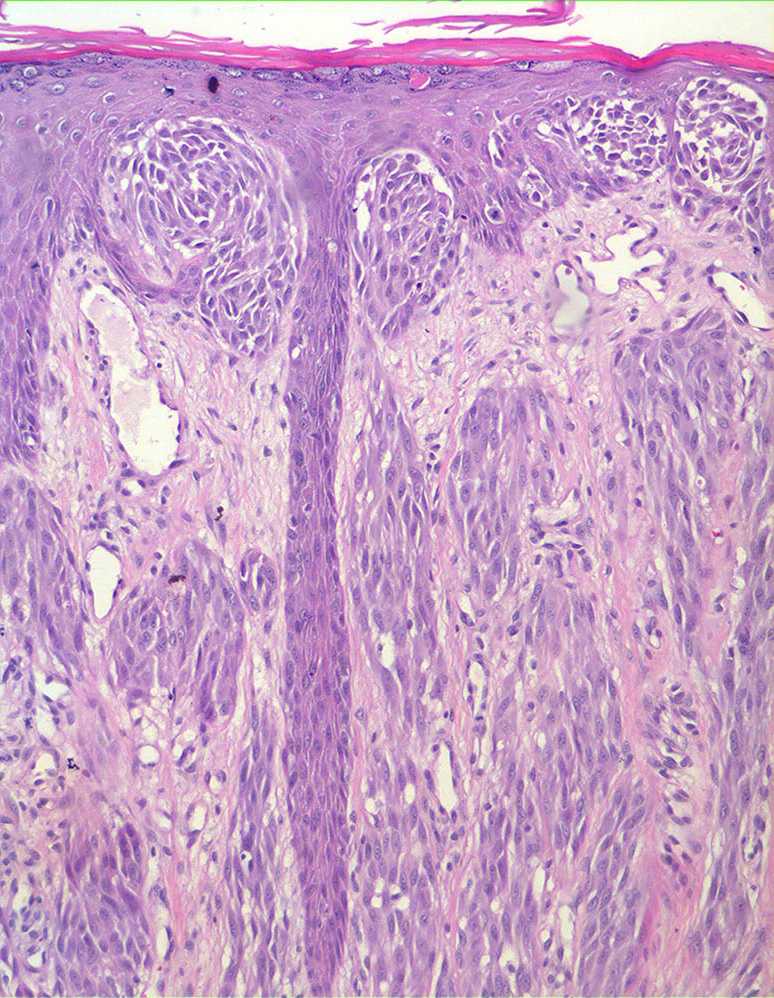

Spitz naevus (juvenile melanoma) = وحمة سبيتز _الميلانوم الفتوي